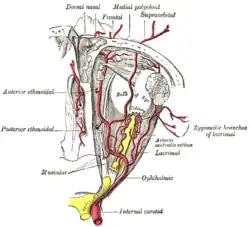

C6: Ophthalmic segment

The ophthalmic segment, or C6, extends from the distal dural ring, which is continuous with the falx cerebri, to the origin of the posterior communicating artery. The ophthalmic segment courses roughly horizontally, parallel to the optic nerve, which runs superomedially to the carotid at this point.

The named branches of the ophthalmic segment are:

- the ophthalmic artery

- the superior hypophyseal artery